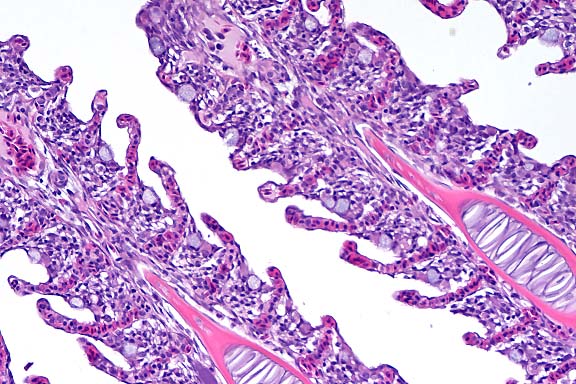

- The lung has multiple, discrete, subpleural granulomas which

each contain a single immature cestode that lacks a bladder wall.

The cestode larvae are nonsegmented and contain an invaginated

scolex. Occasional sections of the larvae show the presence of

suckers in the invaginated canal. Larvae have multiple small

lightly basophilic calcareous corpuscles. The reaction is characterized

by fibrous septal thickening, type II pneumocyte hyperplasia

and a mix of inflammatory cells consisting of eosinophils, macrophages,

plasma cells, and lymphocytes. A layer of degenerate inflammatory

cells lies adjacent to the cestodes. The pleura is thickened

by chronic pleuritis.

- Case 8-1 . Lung. The 2x view shows 3 profiles of cestode

larva surrounded by a dense inflammatory infiltrate forming a

granuloma adjacent to the pleura surface. Surrounding alveoli

have mild alveolar emphysema and thickened alveolar septa. At

40x, multiple calcarious corpuscles (blue bodies with clear halos)

are scattered within the mesenchyme of the larva. The tegument

has a thick eosinophilic, 15-20u, smooth surfaced cuticle. The

surrounding interstitium is fibrotic with moderate numbers of

infiltrating eosinophils and fewer macrophages and lymphocytes.